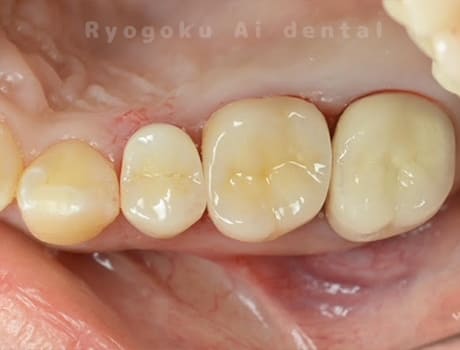

- 原因

- 重度カリエス

-

- 治療内容

- マイクロエンド

- 治療費用

- 77,000円

- 担当医

- Dr. 炭野

虫歯が大きく、神経の保存ができなかったため、マイクロエンド治療を行いました。